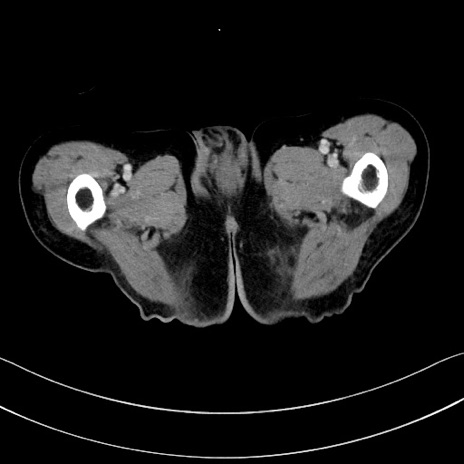

冠状断像

【症例】60歳代男性

【現病歴】胃癌にて胃全摘後。食思不振が悪化し、夜中に嘔吐することがある。

【既往歴】胃癌、胃全摘、脾摘、胆摘後